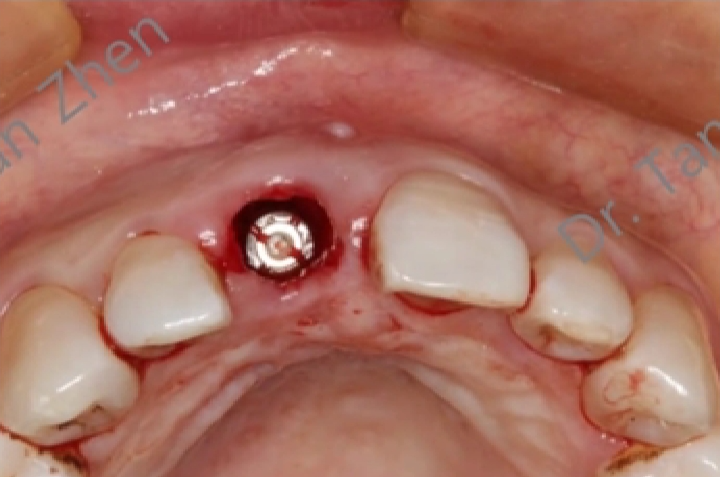

术后愈合:

-

旋转瓣的使用可以保护种植区域,使其在术后正常愈合,减少外界干扰。

这种保护作用对于避免骨移植材料暴露和种植体周围感染至关重要。